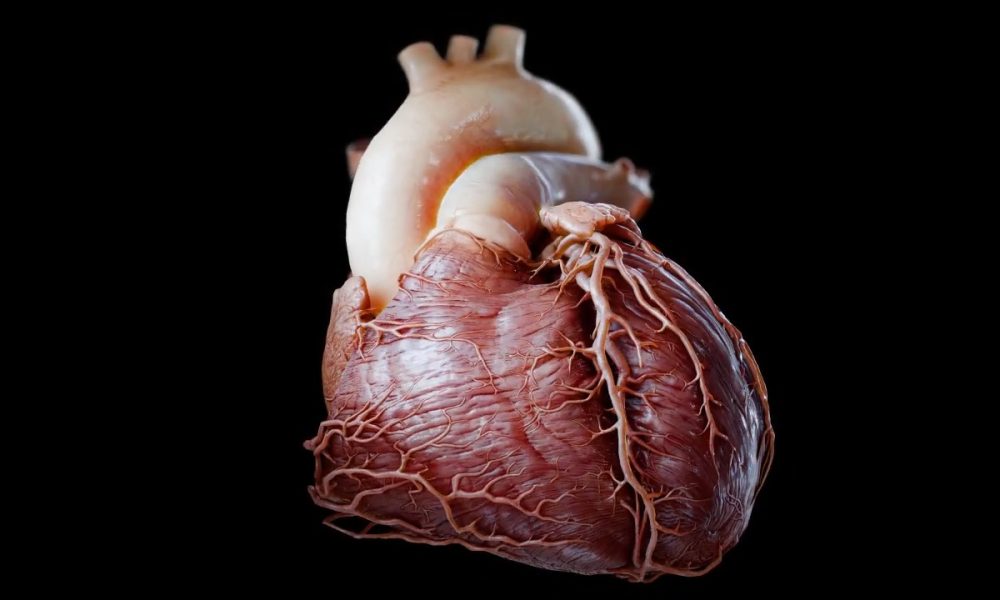

Would you believe this wasn’t shot on a real…